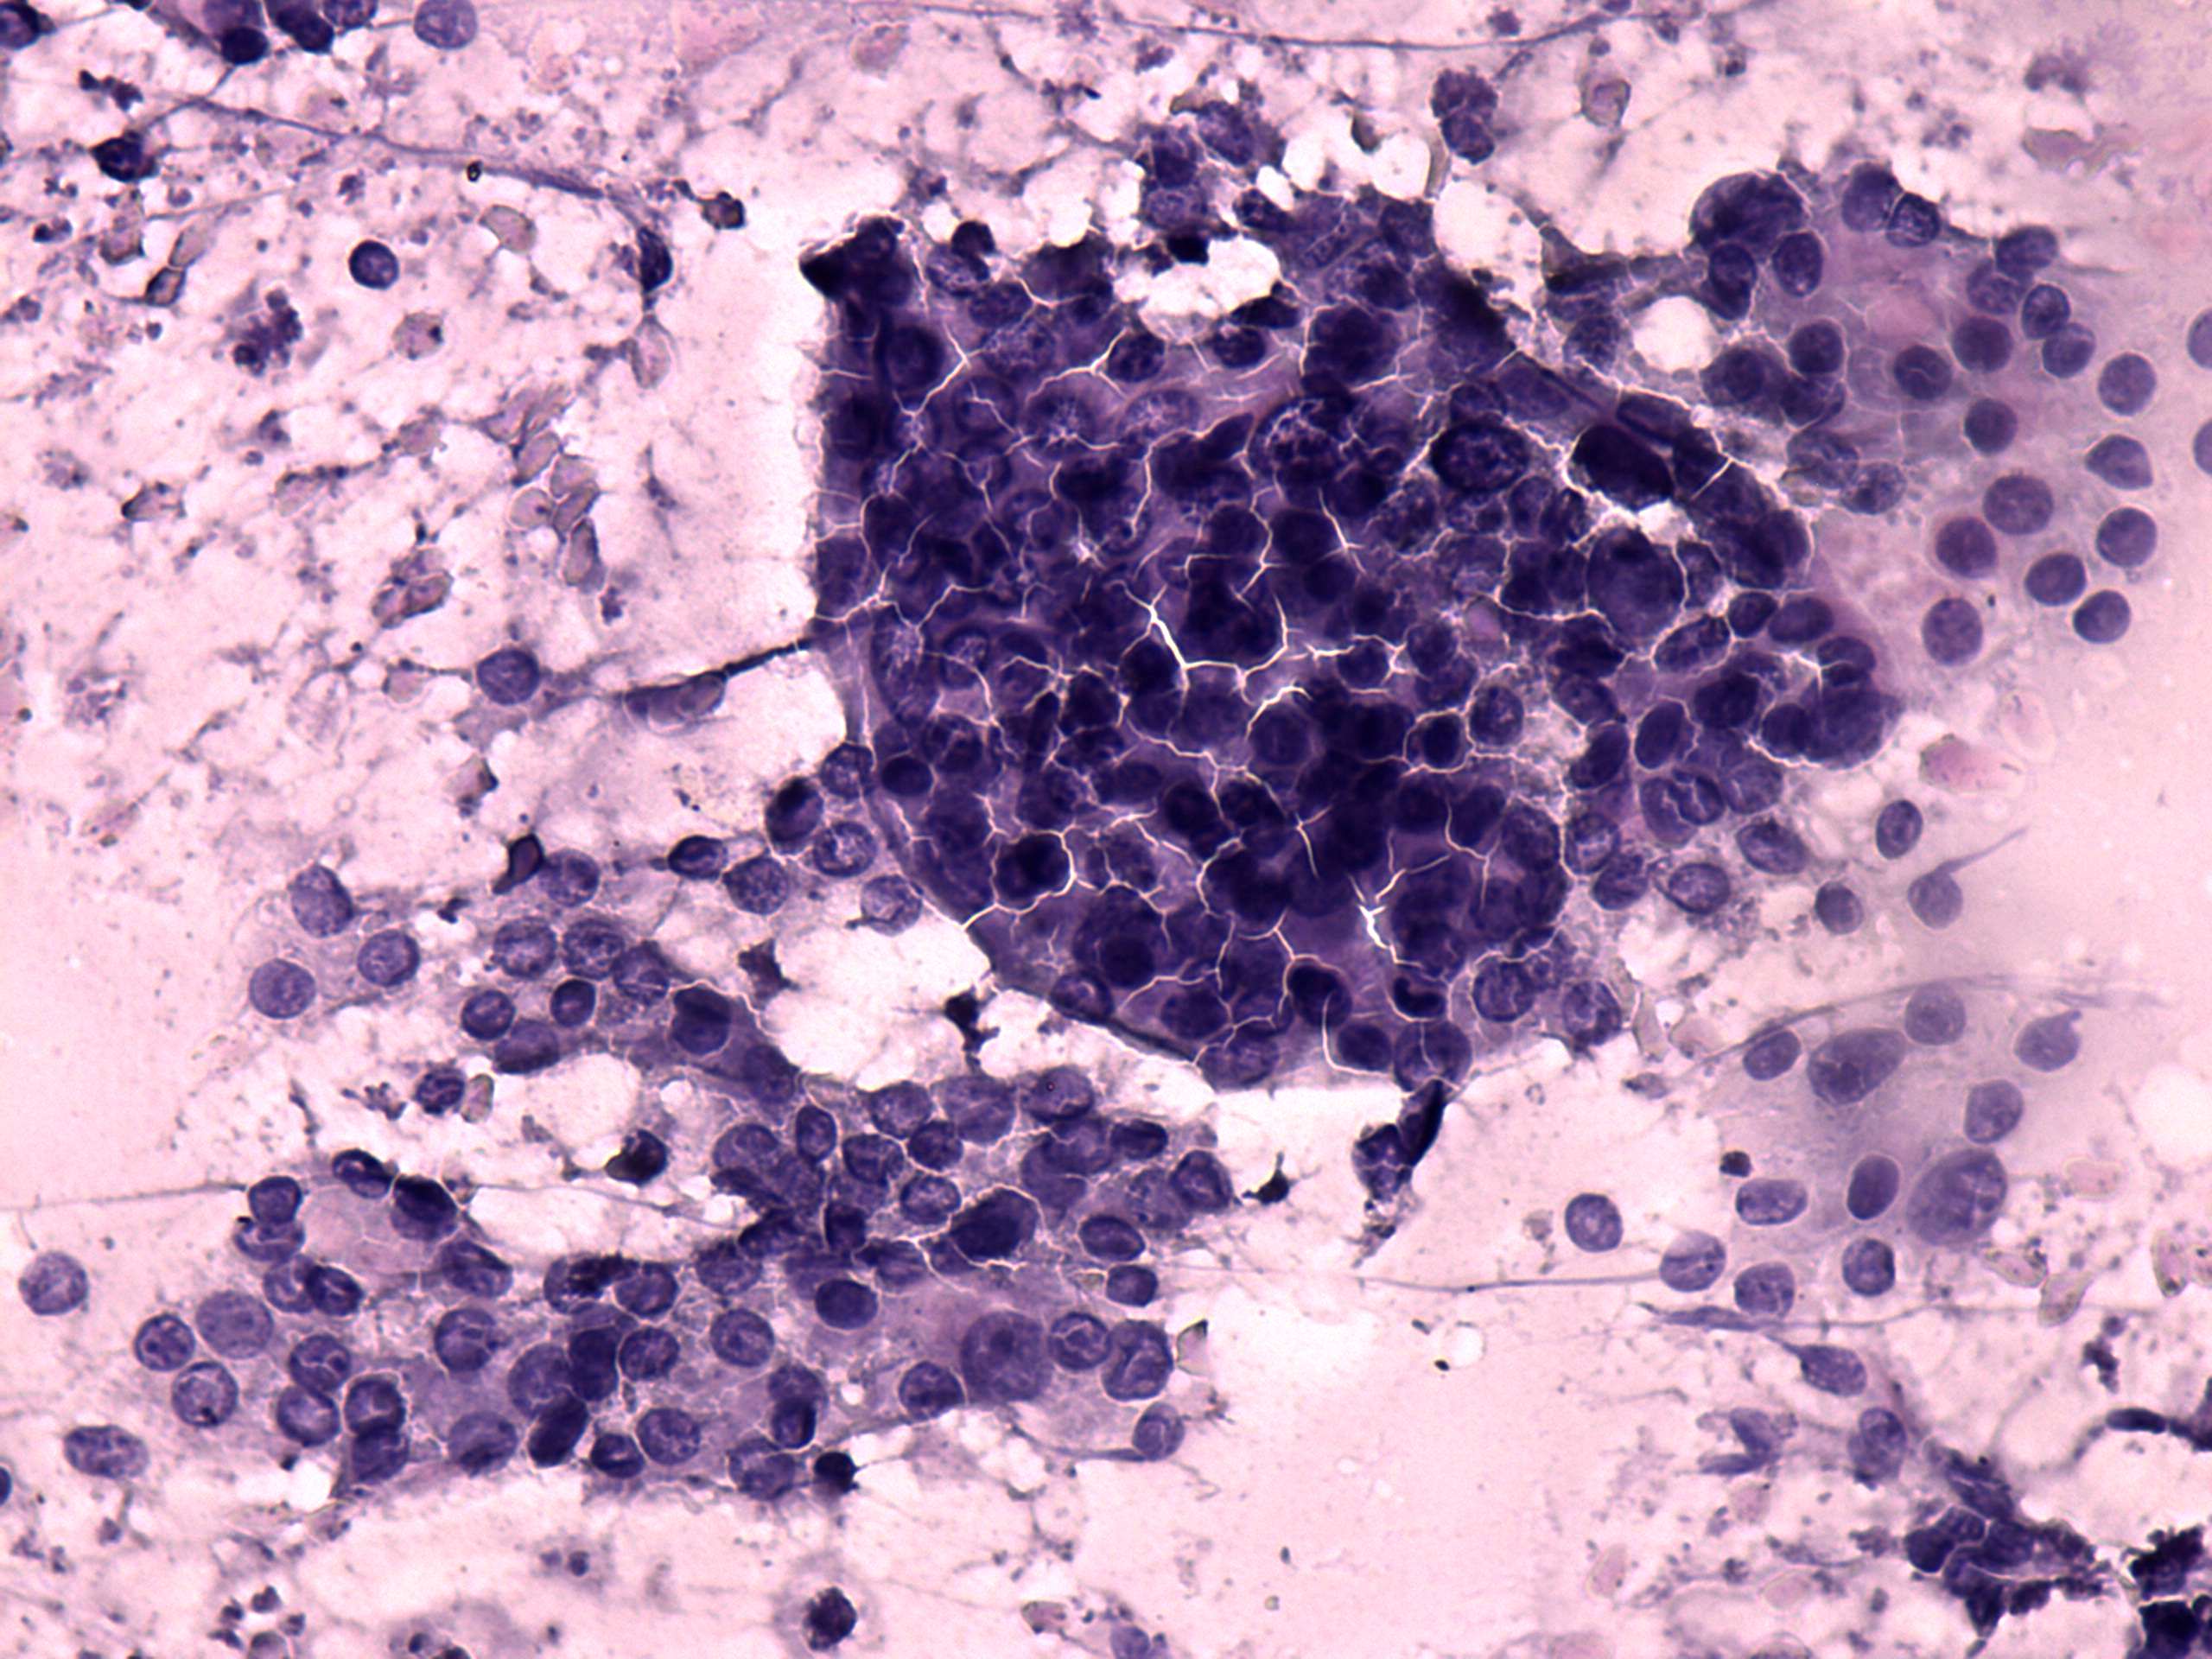

Chronic lymphocytic thyroiditis - Case 38. (cytologic picture 5)

Pap-smear, 400x. The cell groups are composed of thyrocytes mixed with a few lymphoid cells. Follicular cells exhibit occasionally prominent nucleoli, but do not show significant atypia.